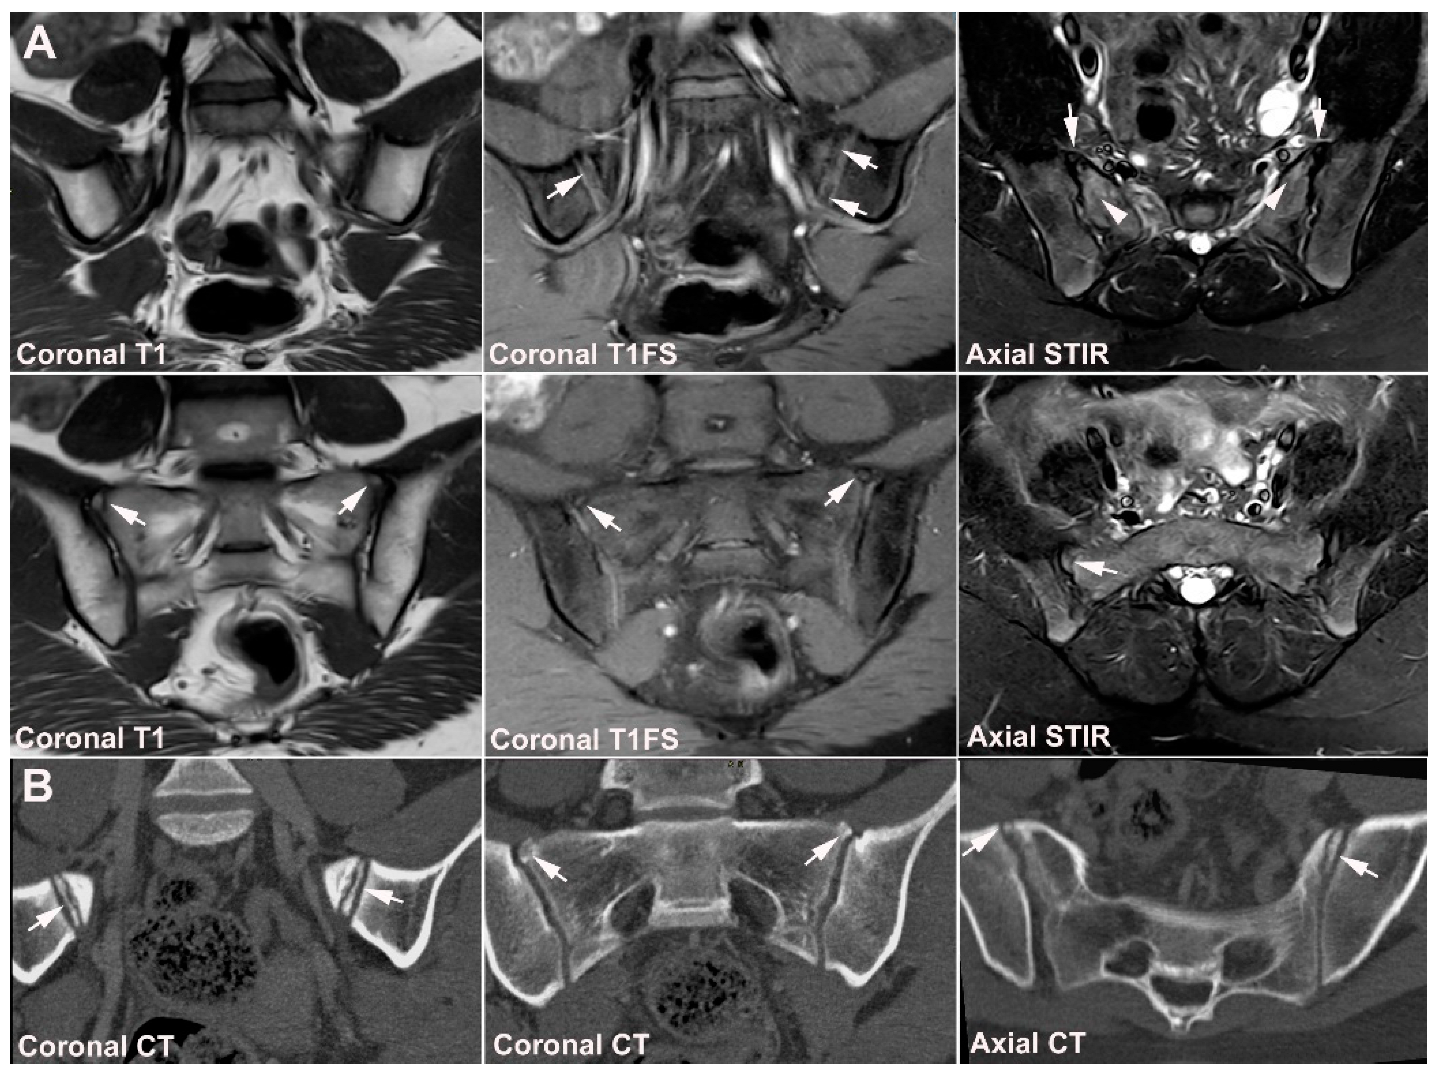

9. Infectious Sacroiliitis

10. Fractures

11.1. Other Types of Arthritis, Including Gout and Pseudo-Gout

11.2. Chronic Non-Bacterial Osteitis (CNO)